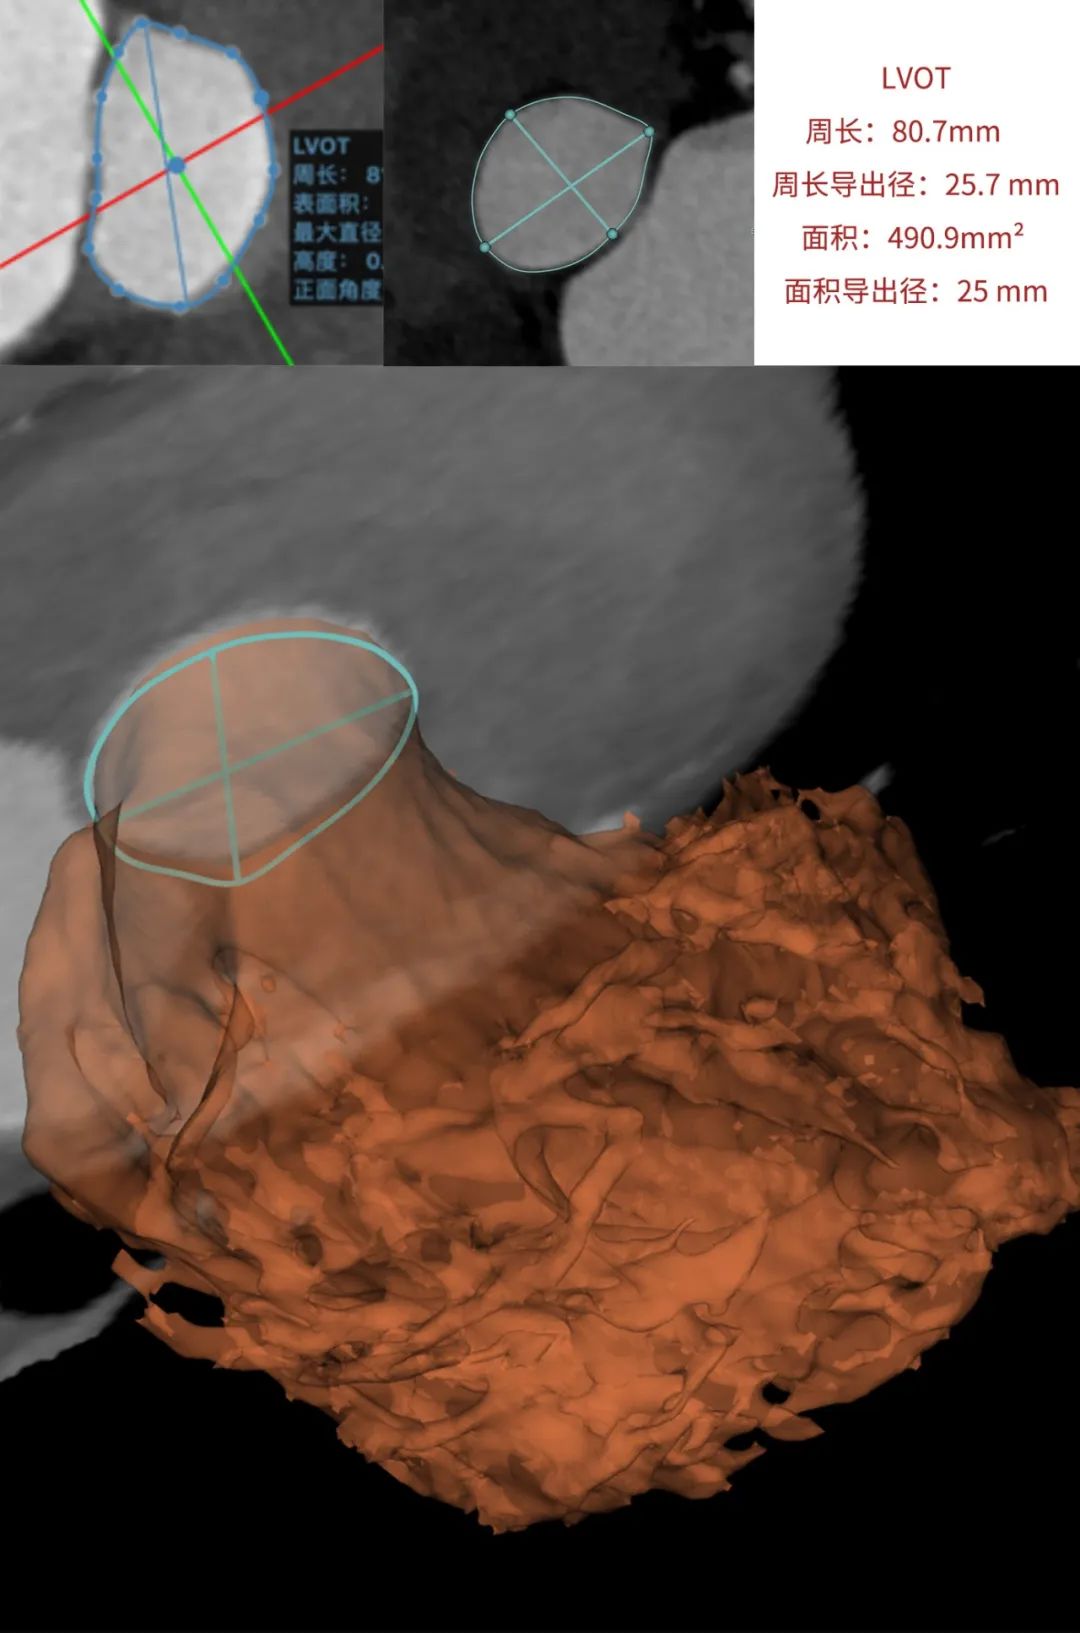

临床团队同时使用了基于医生手工描点的围术期影像评估软件和基于人工智能的瓣膜疾病围术期分析辅助决策软件进行术前影像学评估。

通过术前测量,对病例深入分析,结合人工智能术前分析辅助决策软件进行三维和二维图像融合,郭应强教授指出本例手术存在以下难点:

选择植入Xcor-26瓣膜,充分利用支撑臂避免瓣膜移位发生。